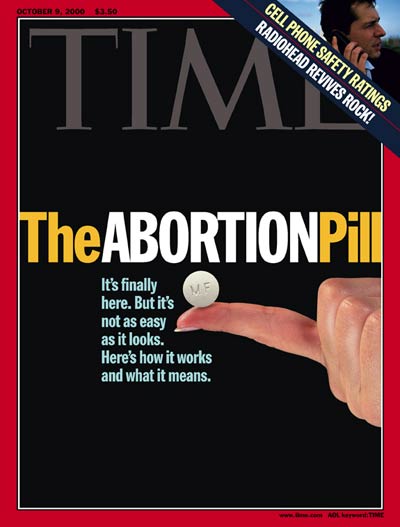

她说:“医疗机构在过去40年也发生了很多变化,因为法令的限制,现在已经没有手术医生,而是更多地施行药物流产,这同样也存在很多的问题。”